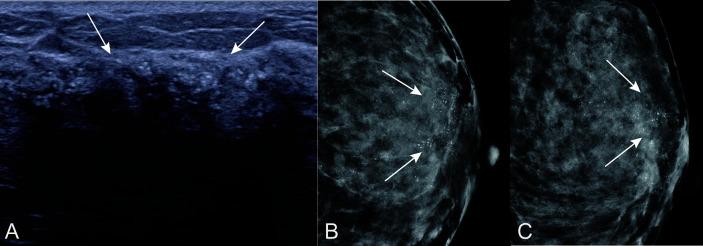

The rate of carcinoma upgrade for atypical ductal hyperplasia (ADH) diagnosed on core needle biopsy (CNB) is variable on open excision. The purpose of the present study was to develop and validate a simple-to-use nomogram for predicting the upgrade of ADH diagnosed with ultrasound (US)-guided core needle biopsy in patients with US-detected breast lesions.

Of the 587 ADH biopsies, 67.7% (training set: 267/401, 66.6%; validation set: 128/186, 68.8%) were upgraded to cancers. In the multivariable analysis, the risk factors were age [odds ratio (OR) 2.739, 95% confidence interval (CI): 1.525-5.672], mass palpation (OR 3.008, 95% CI: 1.624-5.672), calcifications on US (OR 4.752, 95% CI: 2.569-9.276), ADH extent (OR 3.150, 95% CI: 1.951-5.155), and suspected malignancy (OR 4.162, CI: 2.289-7.980). The model showed good discrimination, with an area under curve (AUC) of 0.783 (95% CI: 0.736-0.831), and good calibration ( = 0.543). The application of the nomogram in the validation set still had good discrimination (AUC = 0.753, 95% CI: 0.666-0.841) and calibration ( = 0.565). Instead of surgical excision of all ADHs, if those categorized with the model to be at low risk for upgrade were surveillanced and the remainder were excised, then 63.7% (37/58) of surgeries of benign lesions could have been avoided and 78.1% (100/128) malignant lesions could be treated in time.

This study developed a simple-to-use nomogram by incorporating clinicopathological and US features with the overarching goal of predicting the probability of upgrade in women with ADH. The nomogram could be expected to decrease unnecessary surgery by nearly two-third and to identify most of the malignant lesions, helping guide clinical decision making with regard to surveillance surgical excision of ADH lesions.